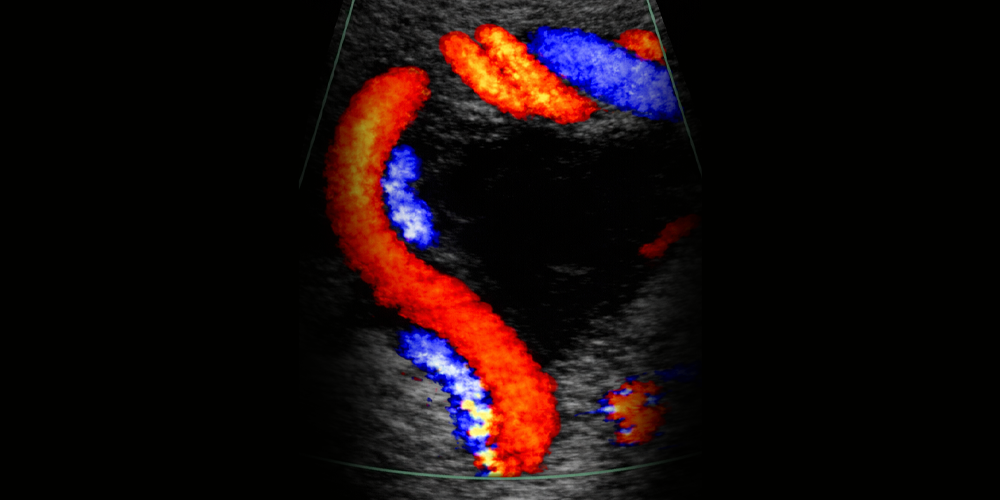

Hareketli kısımları renklendirerek görüntülemek Renkli Doppler diye isimlendirilmiştir. Bu özellik dokular içindeki kan akımlarını incelemek için çok kullanışlıdır.

Yaklaşan akımı farklı, uzaklaşan akımı farklı renkle işaretlemek standart renkli-Dopler yöntemidir.

Yön önemli değil, az da olsa tüm akımı görelim denirse Power Doppler yöntemi kullanılmış olur. Akımı grafik halinde gösteren yönteme de Pulse Doppler (Nabız Dopleri) denir. Aşağıdaki resimde sol altta power Doppler ve sağ altta Pulse Doppler örnekleri görülmektedir.